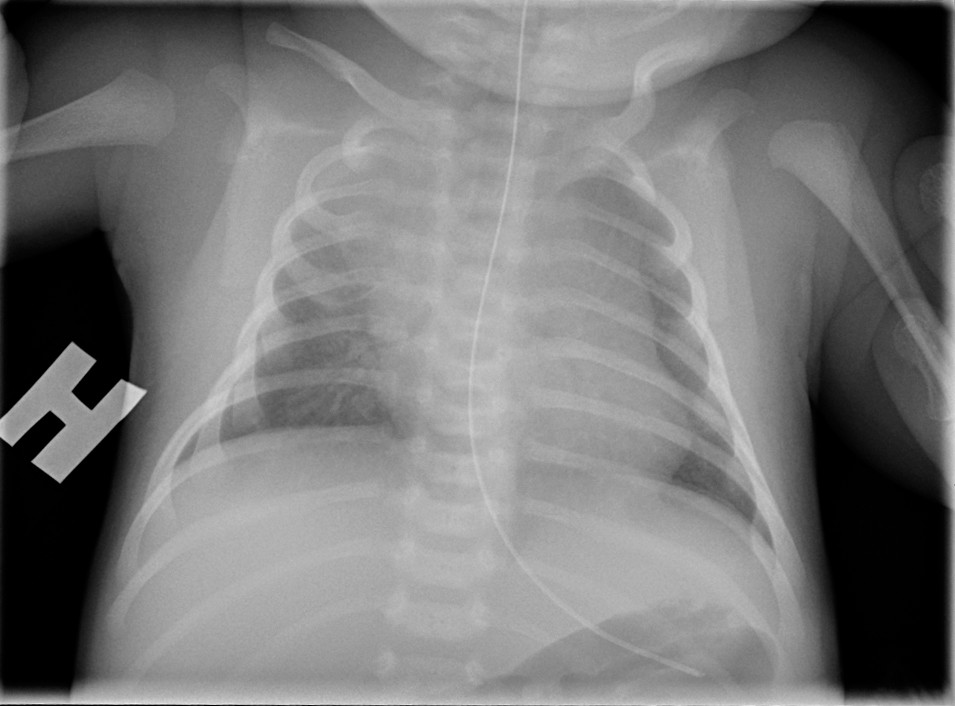

Dag 3 brukte barnet armene sidelikt, og allmenntilstanden var god. CRP steg til 170 mg/l og det vokste gule stafylokokker i blodkultur. Dag 6 ble det observert lett påskyndet respirasjon med normal SpO2. Røntgen thorax viste betydelig breddeforøket hjerteskygge (bilde 2). CRP var da 90 mg/l. Ekkokardiografi viste perikardvæske med preg av pretamponade. Han hadde imidlertid normalt middelblodtrykk på 60 mm Hg og normal hjertefrekvens på 150–160/min. Kapillærfylningstid ble ikke målt, men barnet var klinisk velsirkulert ved overflytning til regionssykehuset, hvor det ble utført ultralydveiledet tapping av perikardvæske. Det var oppvekst av gule stafylokokker i perikardvæsken.